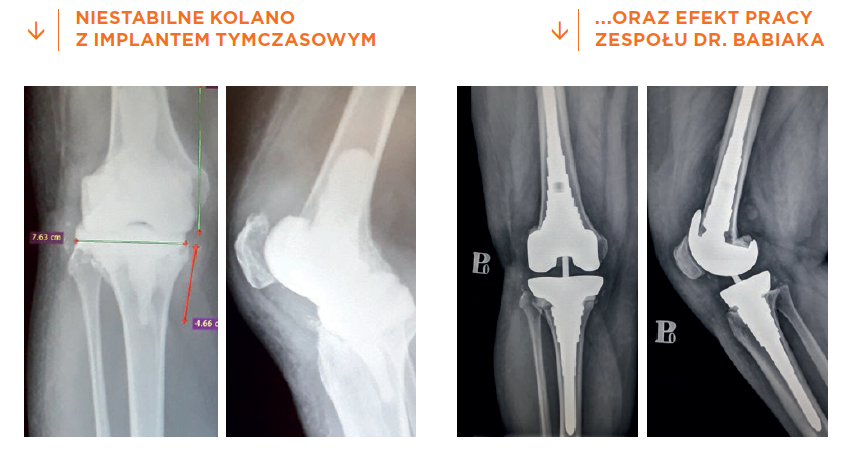

Poważne powikłania po implementacji endoprotezy stawu kolanowego miała inna pacjentka – nauczycielka z północnej Polski. Ponad 3 lata wcześniej wszczepiono jej sztuczny staw kolanowy, jednak po zabiegu odczuwała silny ból i pojawił się stan zapalny. Wykonano więc dwie artroskopowe operacje kolana, które jednak nie poprawiły sytuacji. Konsekwencją było usunięcie endoprotezy i wstawienie tymczasowego implantu (tzw. spacera) z antybiotykami, które miały wyleczyć stan zapalny. Kolano było jednak zupełnie niestabilne, co uniemożliwiało chodzenie. Wtedy pacjentka trafiła do doktora Ireneusza Babiaka z Carolina Medical Center. Wyzwań stojących przed zespołem medycznym było wiele: duży ubytek kostny wywołany infekcją oraz po usunięciu wcześniej wszczepionego implantu, do tego przykurcze oraz obecność blizn po kilku ingerencjach chirurgicznych. Operacja wymagała niesłychanej precyzji, dokładnego planowania, przygotowania i doboru odpowiedniej jakości implantów.

W październiku 2019 roku pacjentka przeszła w naszej klinice operację, w trakcie której usunięty został tymczasowy implant z kolana, a następnie wszczepiona nowoczesna tytanowa endoproteza rewizyjna. Ma ona podłużne trzpienie poprawiające prawidłowe osadzenie i stabilność implantu w kości udowej i piszczelowej oraz stożkowe elementy uzupełniające ubytki kości. Dodatkowo, aby zmniejszyć ryzyko wznowy stanu zapalnego, zastosowano wchłanialne gąbki kolagenowe z antybiotykami, a do zamocowania niektórych elementów endoprotezy specjalny cement kostny z antybiotykami. Dzień po operacji pacjentka zaczęła rehabilitację i chodzenie,a po 4 dniach mogła już o własnych siłach opuścić naszą klinikę. Po zaledwie 2 tygodniach zginała kolano na tyle, że mogła usiąść na normalnym krześle, całkowicie ustąpiła niestabilność stawu kolanowego, rana wygoiła się. Ostatecznie pacjentka cieszy się z odzyskanej po długim czasie sprawności.